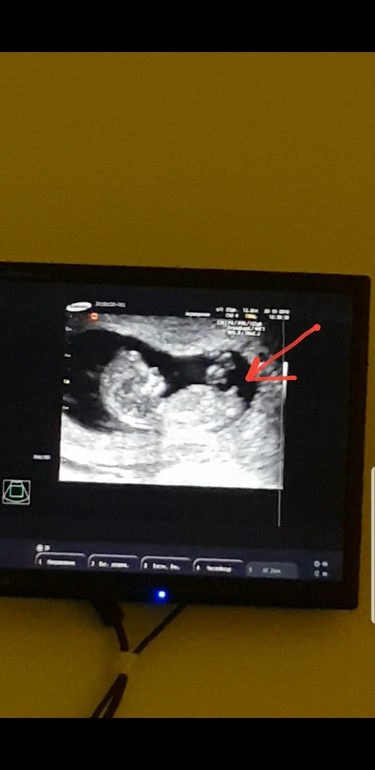

УЗИ, КТГ, доплерКакая вообще статистика? Больше интересует, что сказали мальчик, а в итоге была девочка? Мне на 2х узи в рамках 12-13 недель сказали, что очень похоже на мальчика. По фото и по углу полового бугорки смотрю вроде тоже... интересно Так. Следующее узи в 20 ...Вот наше фото, мне интересно похоже на мальчика?))

Насчет вашей картинки ракурс непонятный, писюн обычно сверху лучше виден